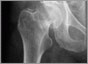

A new model of care that improves access and quality of care for patients with hip and knee arthritis has resulted in a 3M National Quality Health Care Team Award for Sunnybrook's Holland Centre.

The Holland Centre is one of the largest hip and knee joint replacement centres in Canada, performing over 2,200 procedures annually. The 3M Health Care Quality Team Award recognizes three important elements - innovation, quality and teamwork.